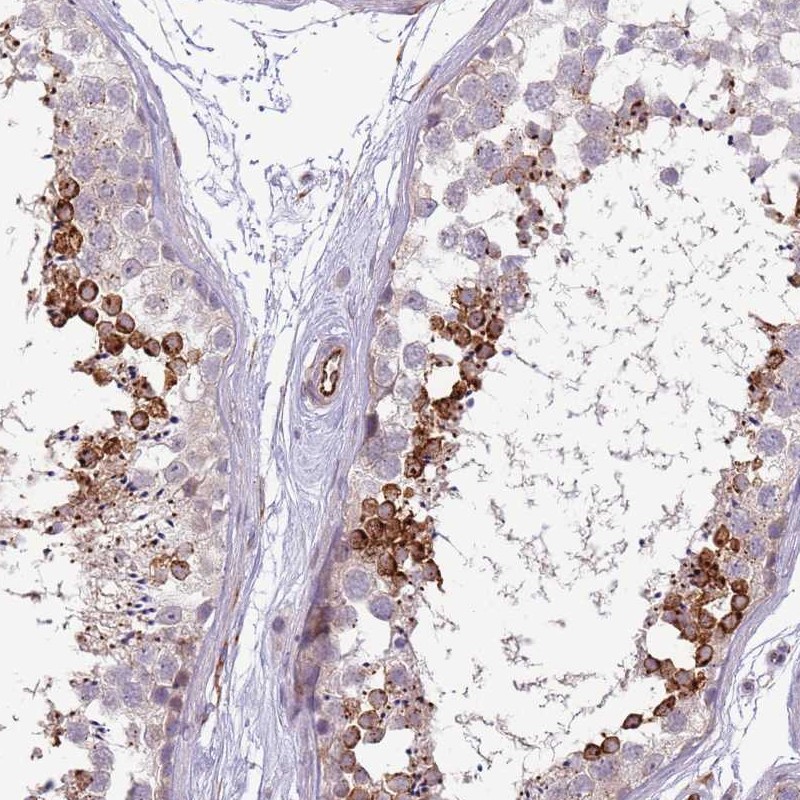

Immunohistochemical staining of human testis shows strong cytoplasmic positivity in a subset of cells in seminiferous ducts.